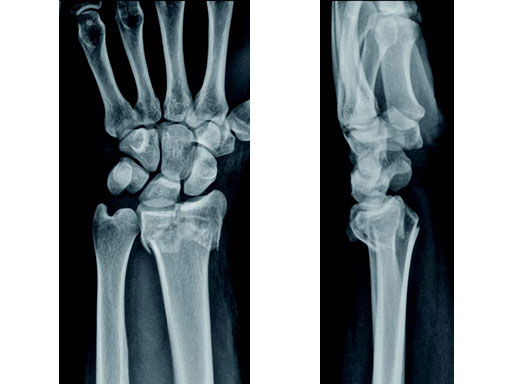

Fig 1a-b Preoperative x-rays.